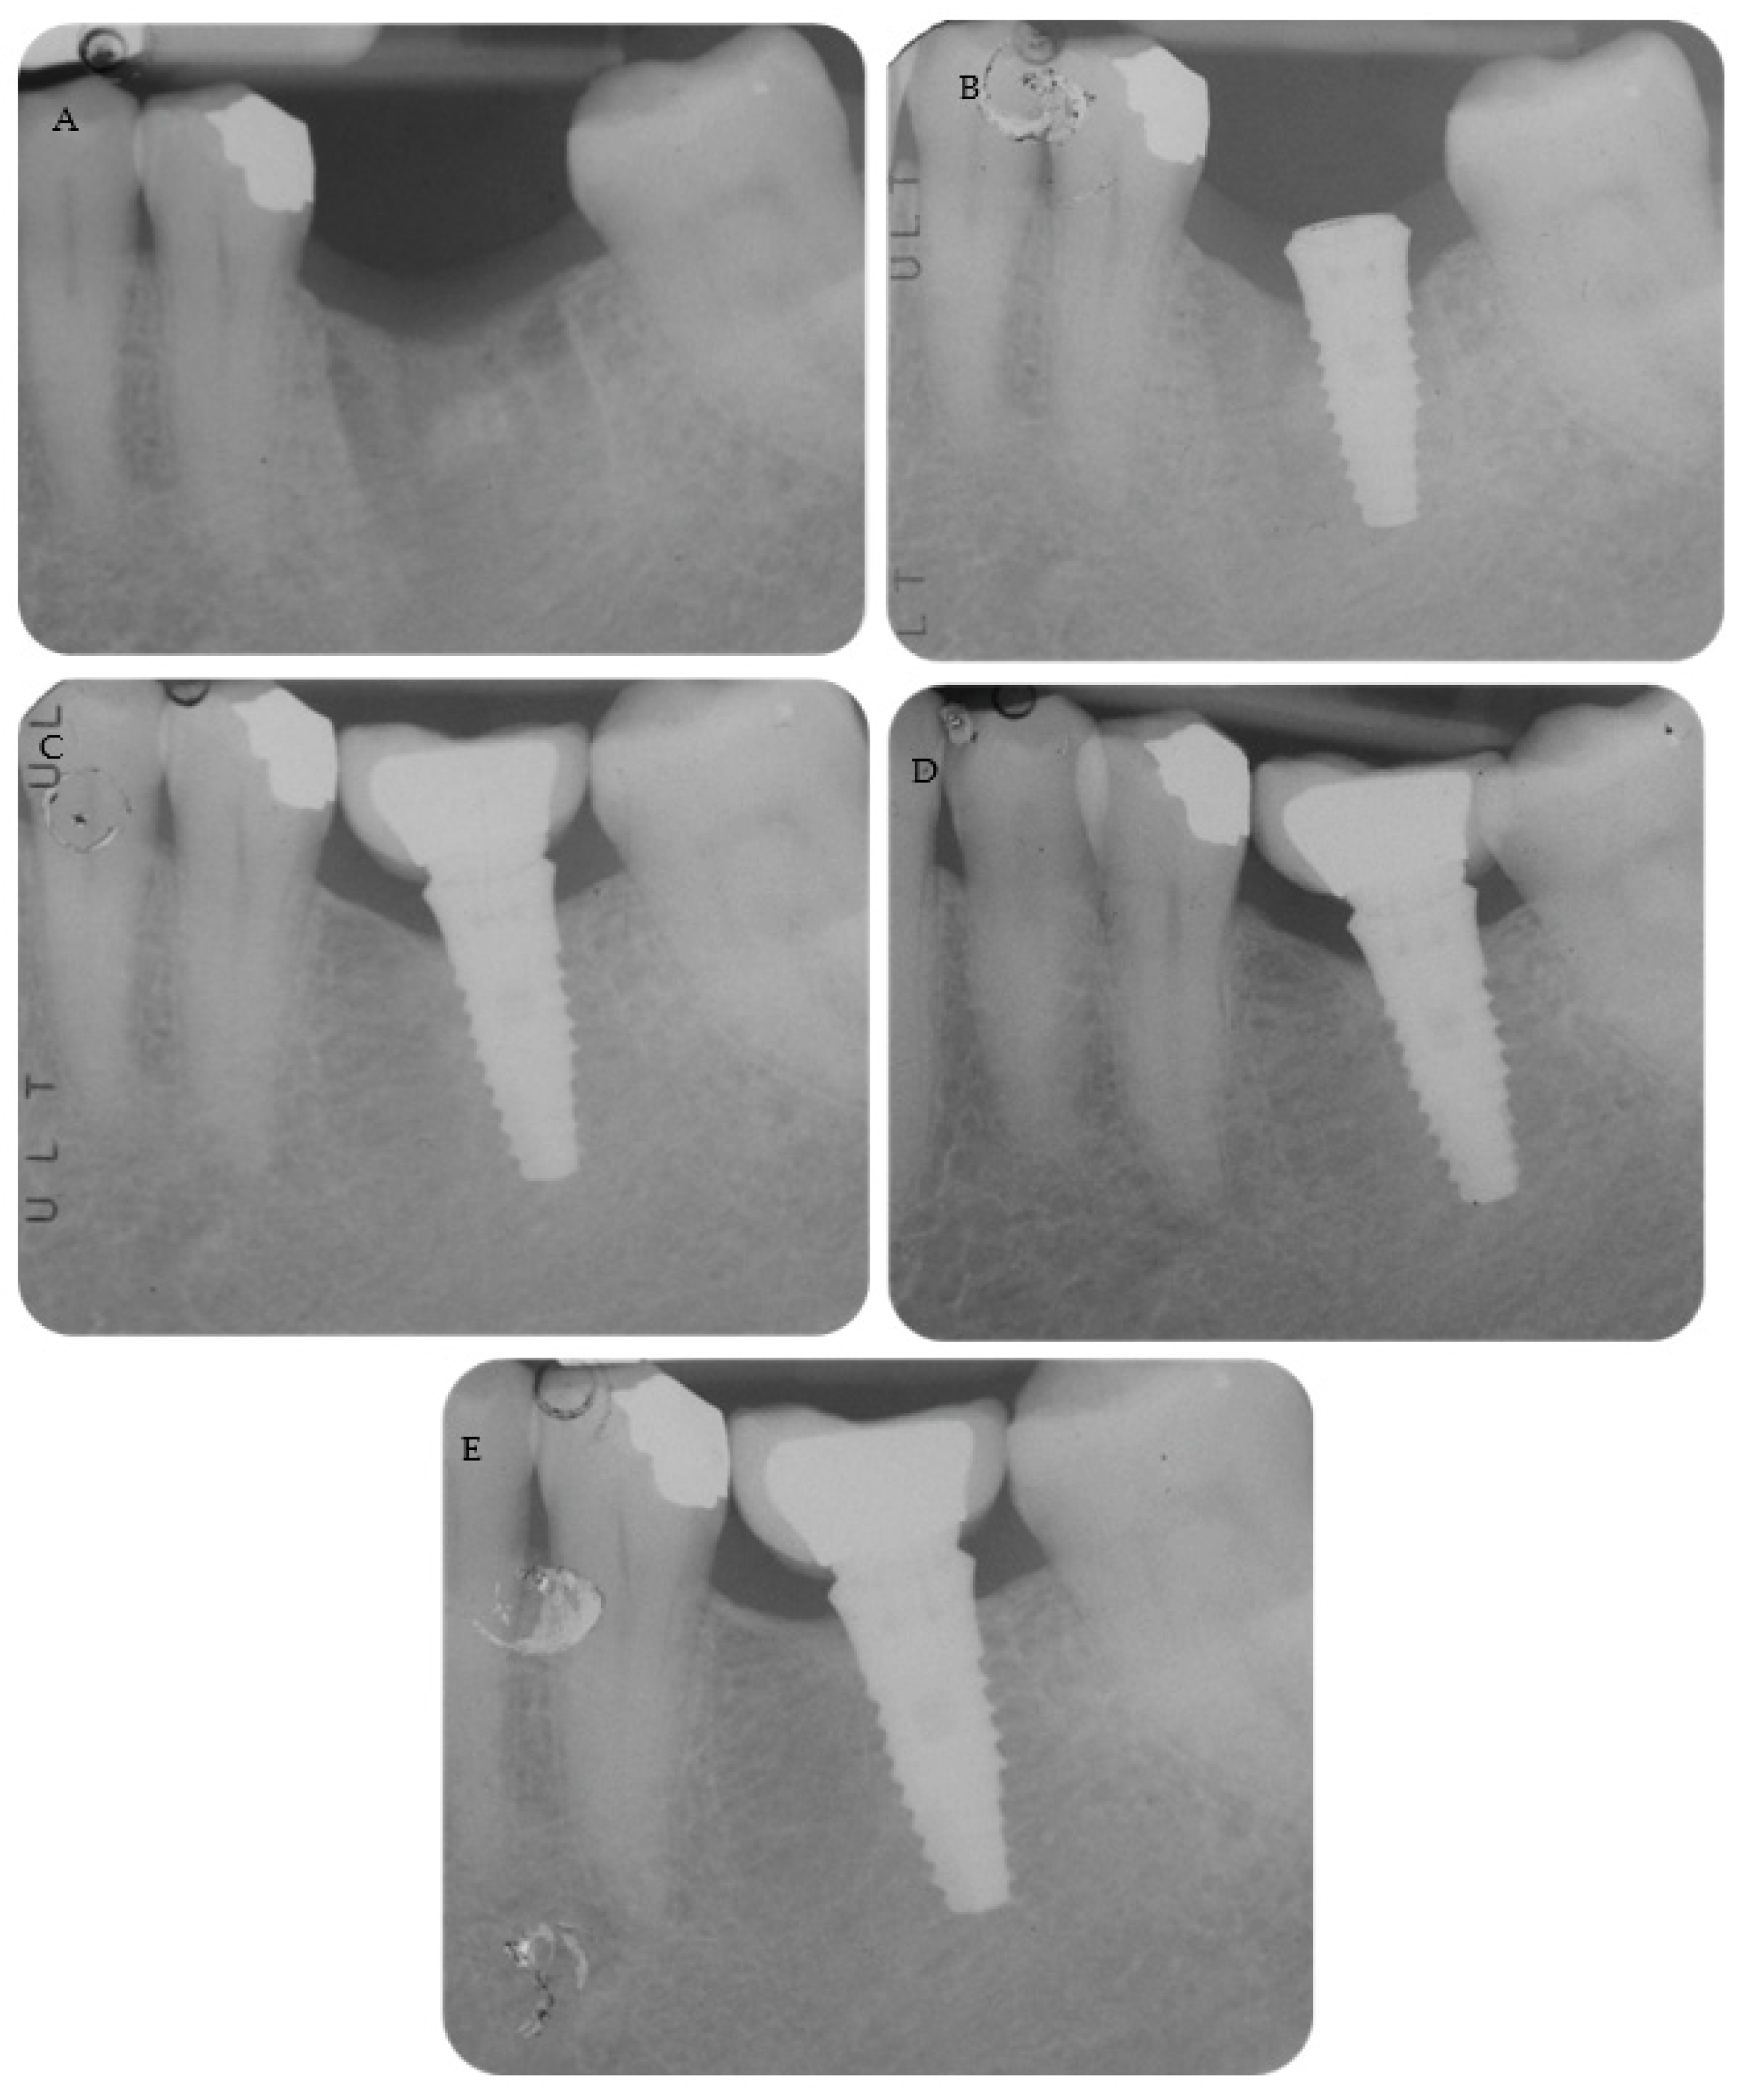

Periapical radiographs reporting two treated cases are shown in Figure 2 and Figure 3.

Figure 2. A 4.6 mm tissue-level implant was placed with a flapless approach. (A) Pre-operative radiograph. (B) Periapical radiograph shows the abutment screwed and the cemented provisional crown. Follow-up at 3 months. (C) Follow-up at 12 months with the metal ceramic crown cemented on the abutment. MBLs were stable at (D) 36 months and (E) 48 months, with limited bone loss.